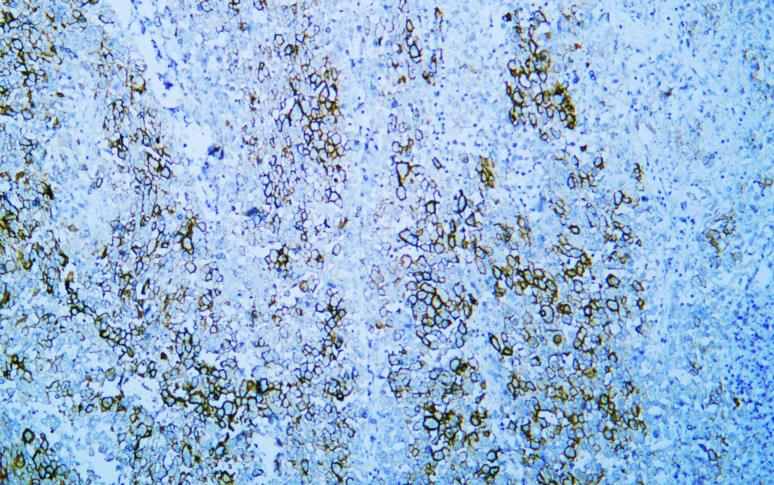

Mesothelin (AB1563) mouse mAb

Application:IHC; WB; IF; ELISA

IHC; WB; IF; ELISA

IHC, 1:200-1:1000 | WB, 1:500-1:2000 | IF, 1:100-1:500 | ELISA, Recommended starting concentration is 1 µg/mL. Please optimize the concentration based on your specific assay requirements.